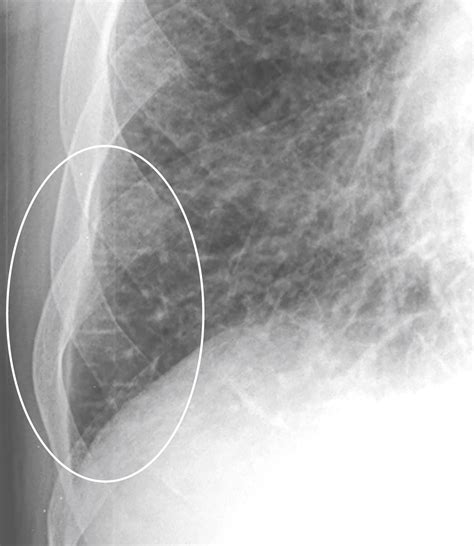

Kerley B lines are radiographic markers that represent thickened interlobular septa. In a healthy lung, these septa are extremely thin and typically invisible on standard posterior-anterior (PA) chest radiographs. However, when fluid accumulates within these spaces—a condition known as interstitial edema—the septa swell, making them dense enough to be visualized as distinct linear opacities.

These lines are distinct because of their specific orientation and location:

• Appearance: They appear as fine, horizontal, unbranching lines.

• Location: They are found primarily at the lung bases, perpendicular to the pleura.

• Length: They are short, usually measuring less than 2 centimeters in length.